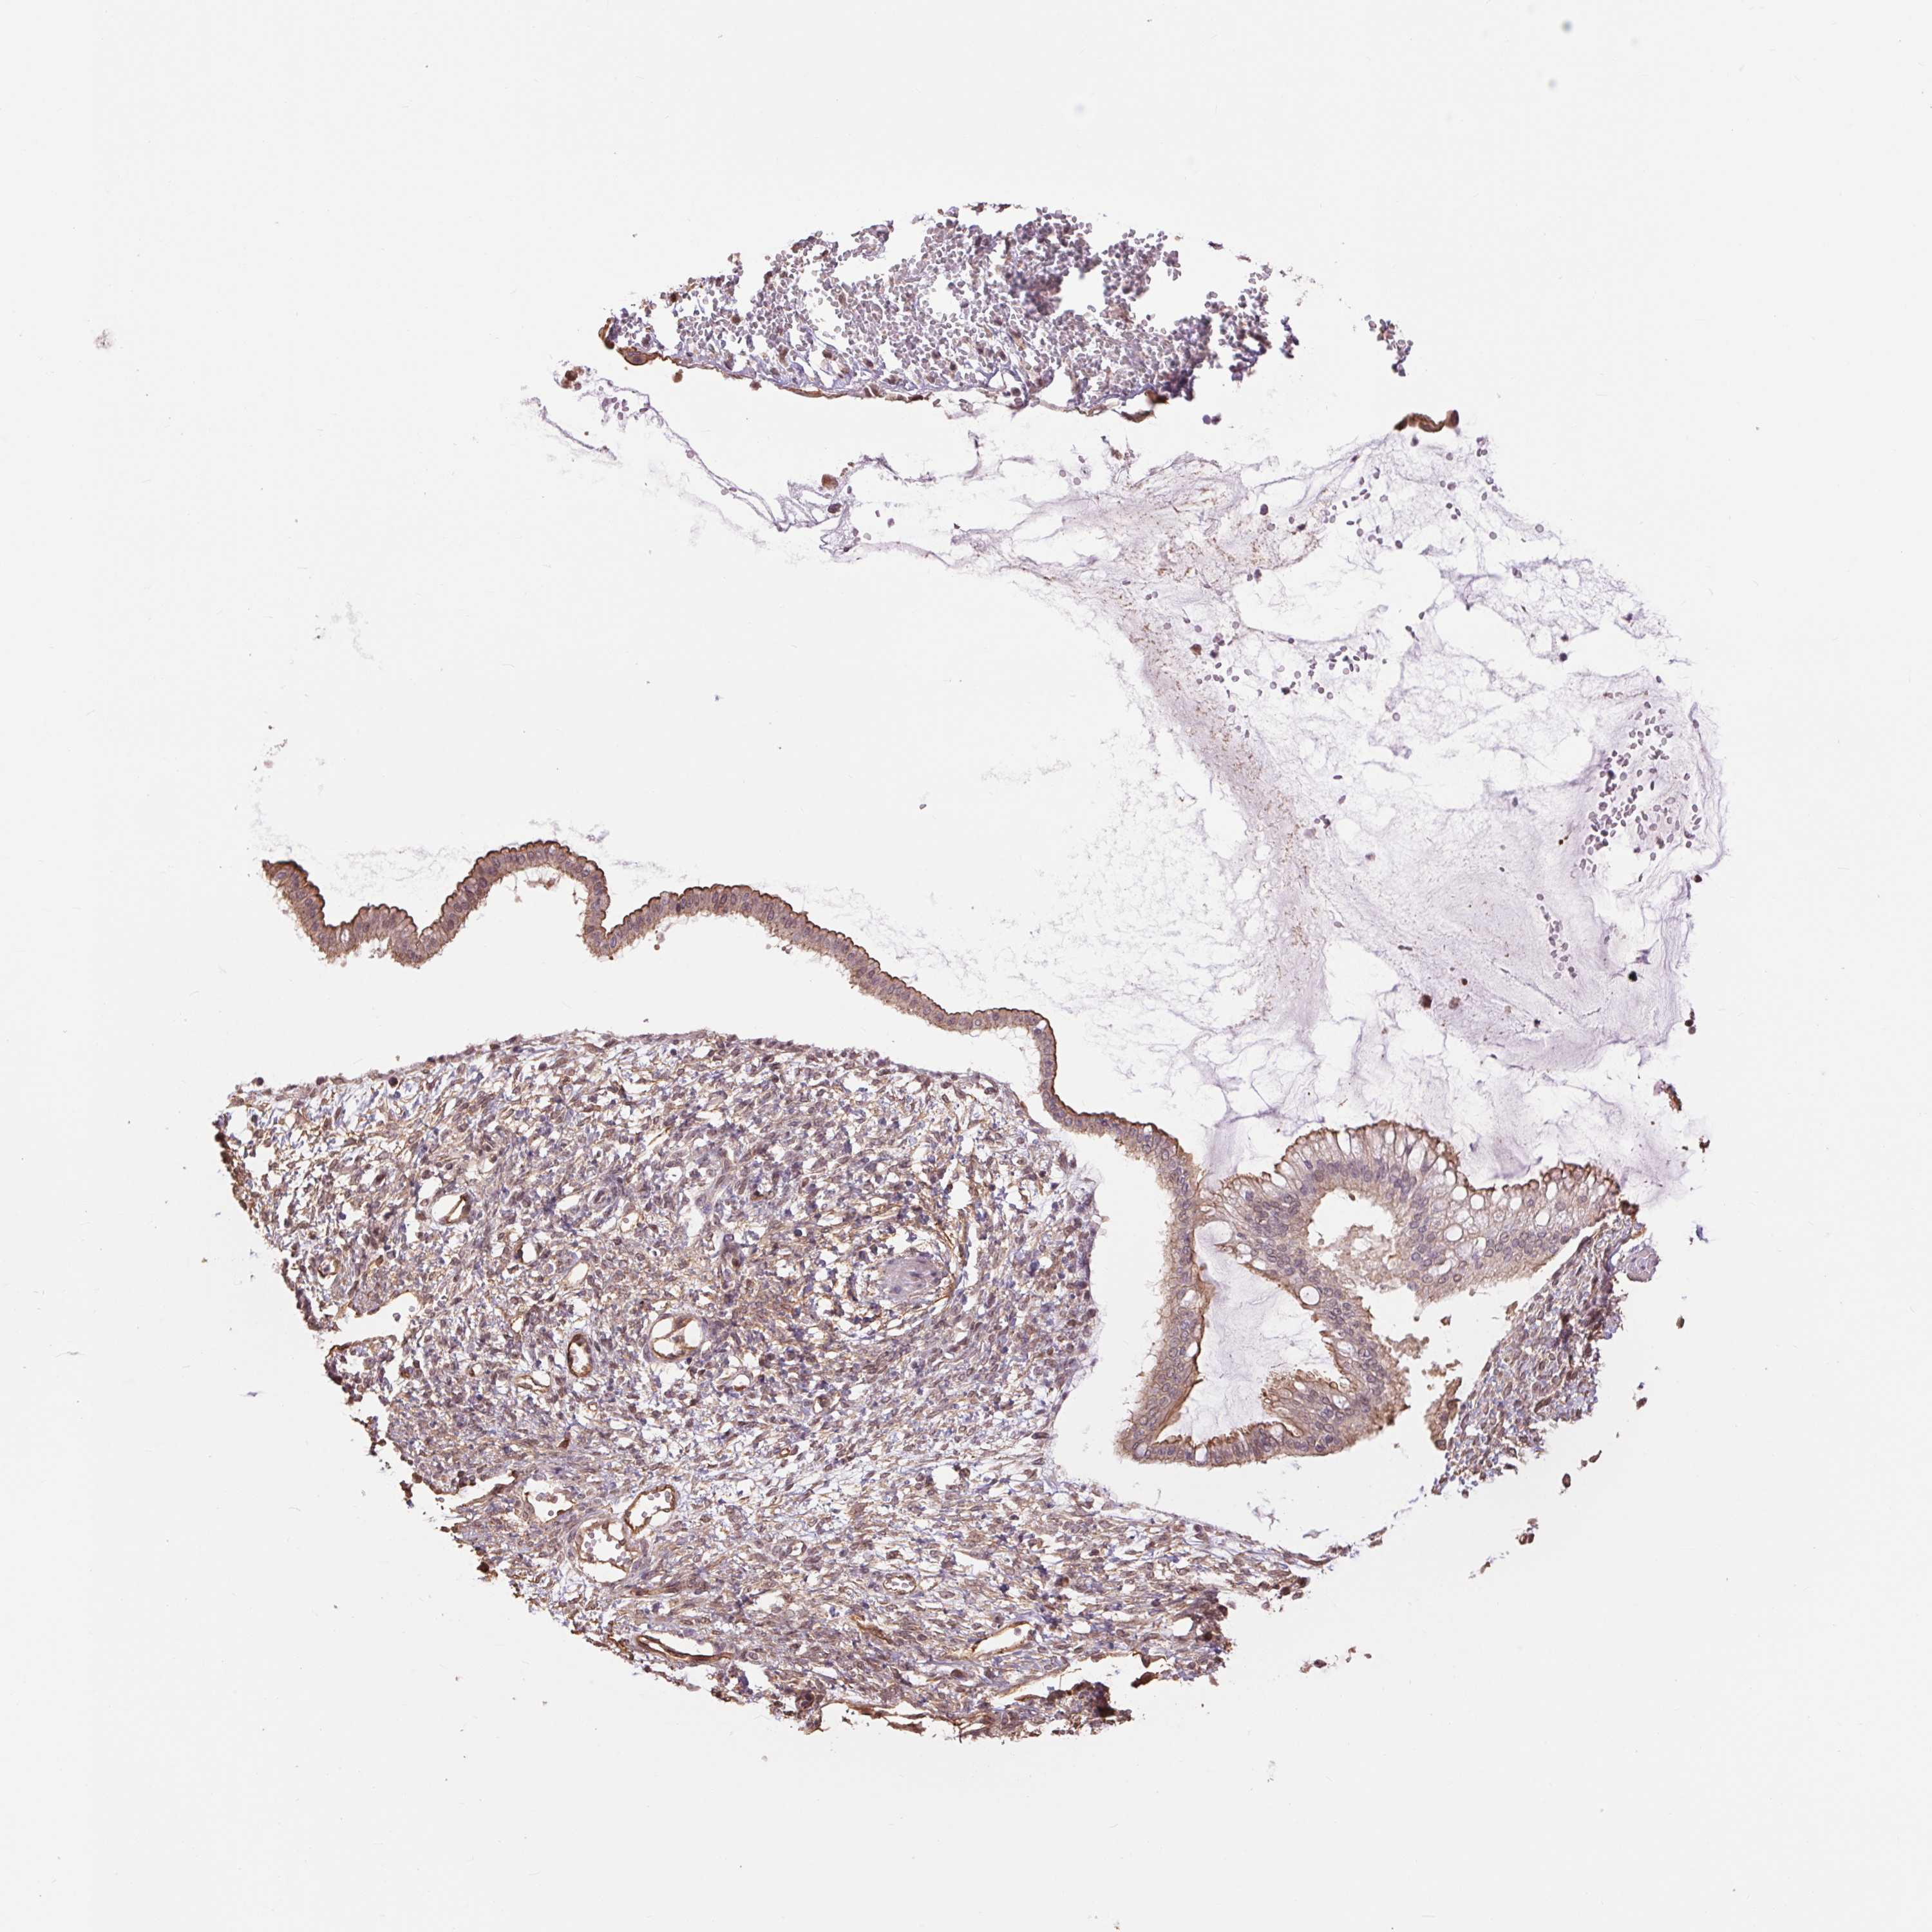

OVARIAN CANCER - Protein expressioni

A mouse-over function shows sample information and annotation data. Click on an image to view it in a full screen mode. Samples can be filtered based on level of antibody staining by selecting one or several of the following categories: high, medium, low and not detected. The assay and annotation is described here.

Note that samples used for immunohistochemistry by the Human Protein Atlas do not correspond to samples in the TCGA dataset.

Antibody stainingi

Antibody staining in the annotated cell types in the current human tissue is reported as not detected, low, medium, or high, based on conventional immunohistochemistry profiling in selected tissues. This score is based on the combination of the staining intensity and fraction of stained cells.

Each image is clickable and will lead to virtual microscopy that enables deeper exploration of all samples and also displays staining intensity scores, fraction scores and subcellular localization as well as patient and tissue information for each sample.

Antibody HPA041713

Antibody HPA049578

Cystadenocarcinoma, serous, NOS

Carcinoma, endometroid

Cystadenocarcinoma, mucinous, NOS

Carcinoma, NOS